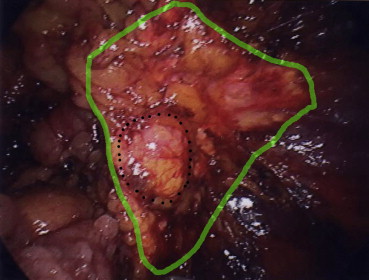

Pathological examination revealed that all adrenal tumors were removed en bloc ( Figure 1 ;  Figure 2). No peri- or postoperative complications occurred. All patients started oral intake and ambulation on the day of the operation. The early cosmetic results were excellent. The hospital stay was 1–6 days (mean, 3 days). None of the patients experienced tumor recurrence during the follow-up period. Fig. 3 shows a representative pre- and postoperative computed tomography of a single patient.

Pre- and postoperative (at 19 months) computed tomography images of a single ...

Figure 3.

Pre- and postoperative (at 19 months) computed tomography images of a single patient. The postoperative image confirmed the successful removal of the adrenal tumor and showed no tumor recurrence.